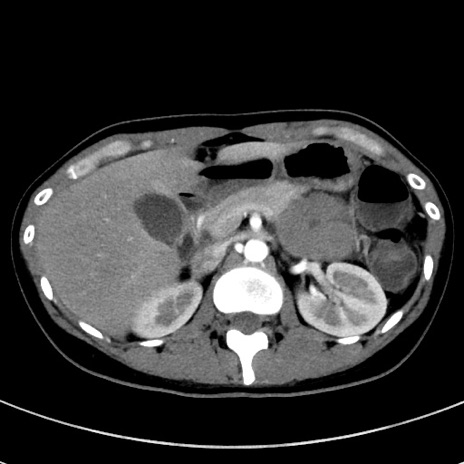

症例17(横断像)

【症例】20歳代女性

【主訴】嘔吐、下腹部痛

【現病歴】昨日夕食後に嘔吐し下腹部痛が出現。本日になっても嘔吐持続し改善しないため来院。

【身体所見】意識清明、BT 37.2℃、BP 108/67mmHg、腹部:平坦、やや硬、下腹部正中から右にかけて圧痛あり、反跳痛軽度あり、tapping pain(+)。

【データ】WBC 13600、CRP 14.94